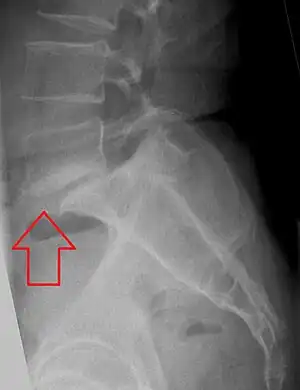

X-ray of the lateral lumbar spine with a grade III anterolisthesis at the L5-S1 level.

Classification by degree of the slippage, as measured as percentage of the width of the vertebral body:[36] Grade I spondylolisthesis accounts for approximately 75% of cases.[23]

• Grade I: 0–25%

• Grade II: 25- 50%

• Grade III: 50–75%

• Grade IV: 75–100%

• Grade V: greater than 100%